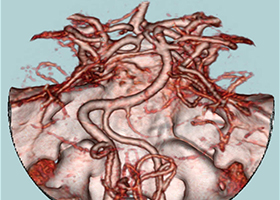

①くも膜下出血の原因となる脳動脈瘤(のうどうみゃくりゅう)の外科治療

63歳女性、左眼視力低下で発症

[画像所見]

左眼の奥に大きな動脈瘤認めます。 -

造影三次元CT画像

左前頭側頭開頭で動脈瘤クリッピング術を行った。手術中は脳血管撮影装置を用いたHybrid手術を施行し、動脈瘤の消失を手術中に確認する。